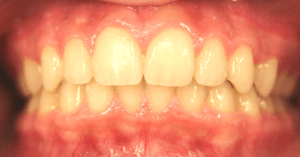

Before and After Photos: Open Bite Correction